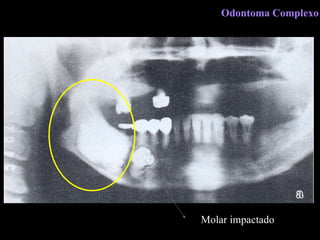

Odontoma Complexo

C l í n i c a Malformação de tecidos dentários. Região de pré-molares e molares, ambos os maxilares. Retenção de dentes. Preferência 1º e 2° décadas. Odontoma Complexo

R a d i o l o g i a  Área radiopaca de limites definidos  Banda radiolúcida periférica Pode se associar a um dente não irrompido Odontoma Complexo

D i a g n ó s t i c o  D i f e r e n c i a l Fibro-odontoma ameloblástico Osteoesclerose Lesões cementárias  Odontoma Complexo

Molar impactado Odontoma Complexo